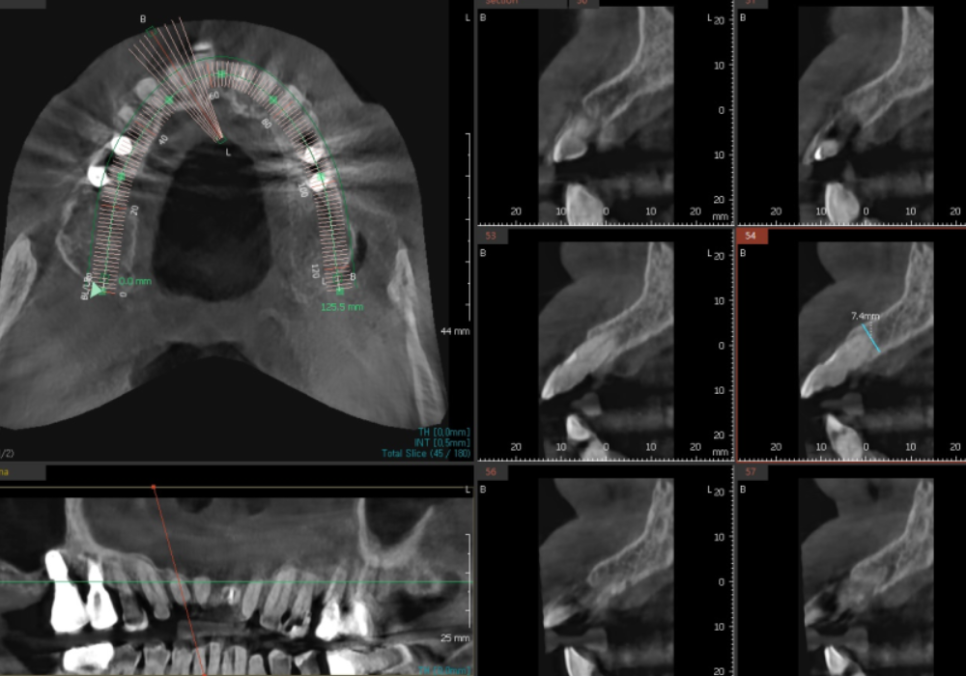

그래서 바로 치료부터 들어가기보다는,

3D CT로 안쪽 상태를

한 번 더 자세히 살펴봤습니다.

다행히

심한 염증은 없었고,

발치 후 즉시 임플란트를 진행할 수 있는

기본적인 조건은 갖추고 있었습니다.

그래서 내원 당일,

앞니 발치와 함께

임플란트 식립을 진행할 수 있었습니다.

수술 전에는

3D CT를 통해 위치를 하나씩 확인하며

계획을 세웁니다.

250221

사실 저는

이 과정을 수술만큼,

어쩌면 그보다 더 중요하게 생각합니다.

그래서 시간을 들여

아주 꼼꼼히 확인합니다.

집을 지을 때도

바로 기둥부터 세우지 않고

기초부터 다시 살펴보는 것처럼,

임플란트도 어디에,

어떤 각도로 세우느냐에 따라

앞으로의 안정성이 크게 달라지기 때문입니다.

여러 각도로 살펴본 결과,

가장 안정적으로 버틸 수 있겠다는

위치를 기준으로 계획을 잡았습니다.